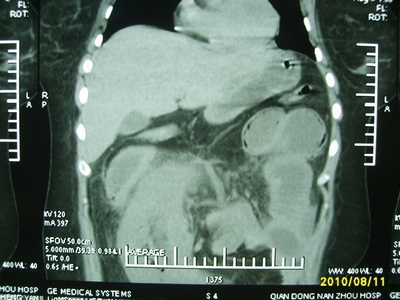

5天前突发腹痛剧烈难忍,伴解淡血水样便。近一天来腹痛缓解,没有明显的腹膜炎的体征。今天照的腹部ct。从ct上看感觉是一个绞窄性肠梗阻,但是现在没有腹痛。不好解释

要有麻烦了,感觉小肠有套叠还有扭转改变,估计部分已有坏死。

高位肠梗阻(不全性),原因小肠(空肠)扭转,肠壁水肿增厚,成年人肠梗阻要排除合并占位,建议手术。

绞窄性肠梗阻_肠管套叠 扭转,肠壁明显水肿。

支持绞窄性肠梗阻,肠壁明显水肿并见有多发小泡状积气--肠坏死

考虑绞窄性肠梗阻并肠坏死。